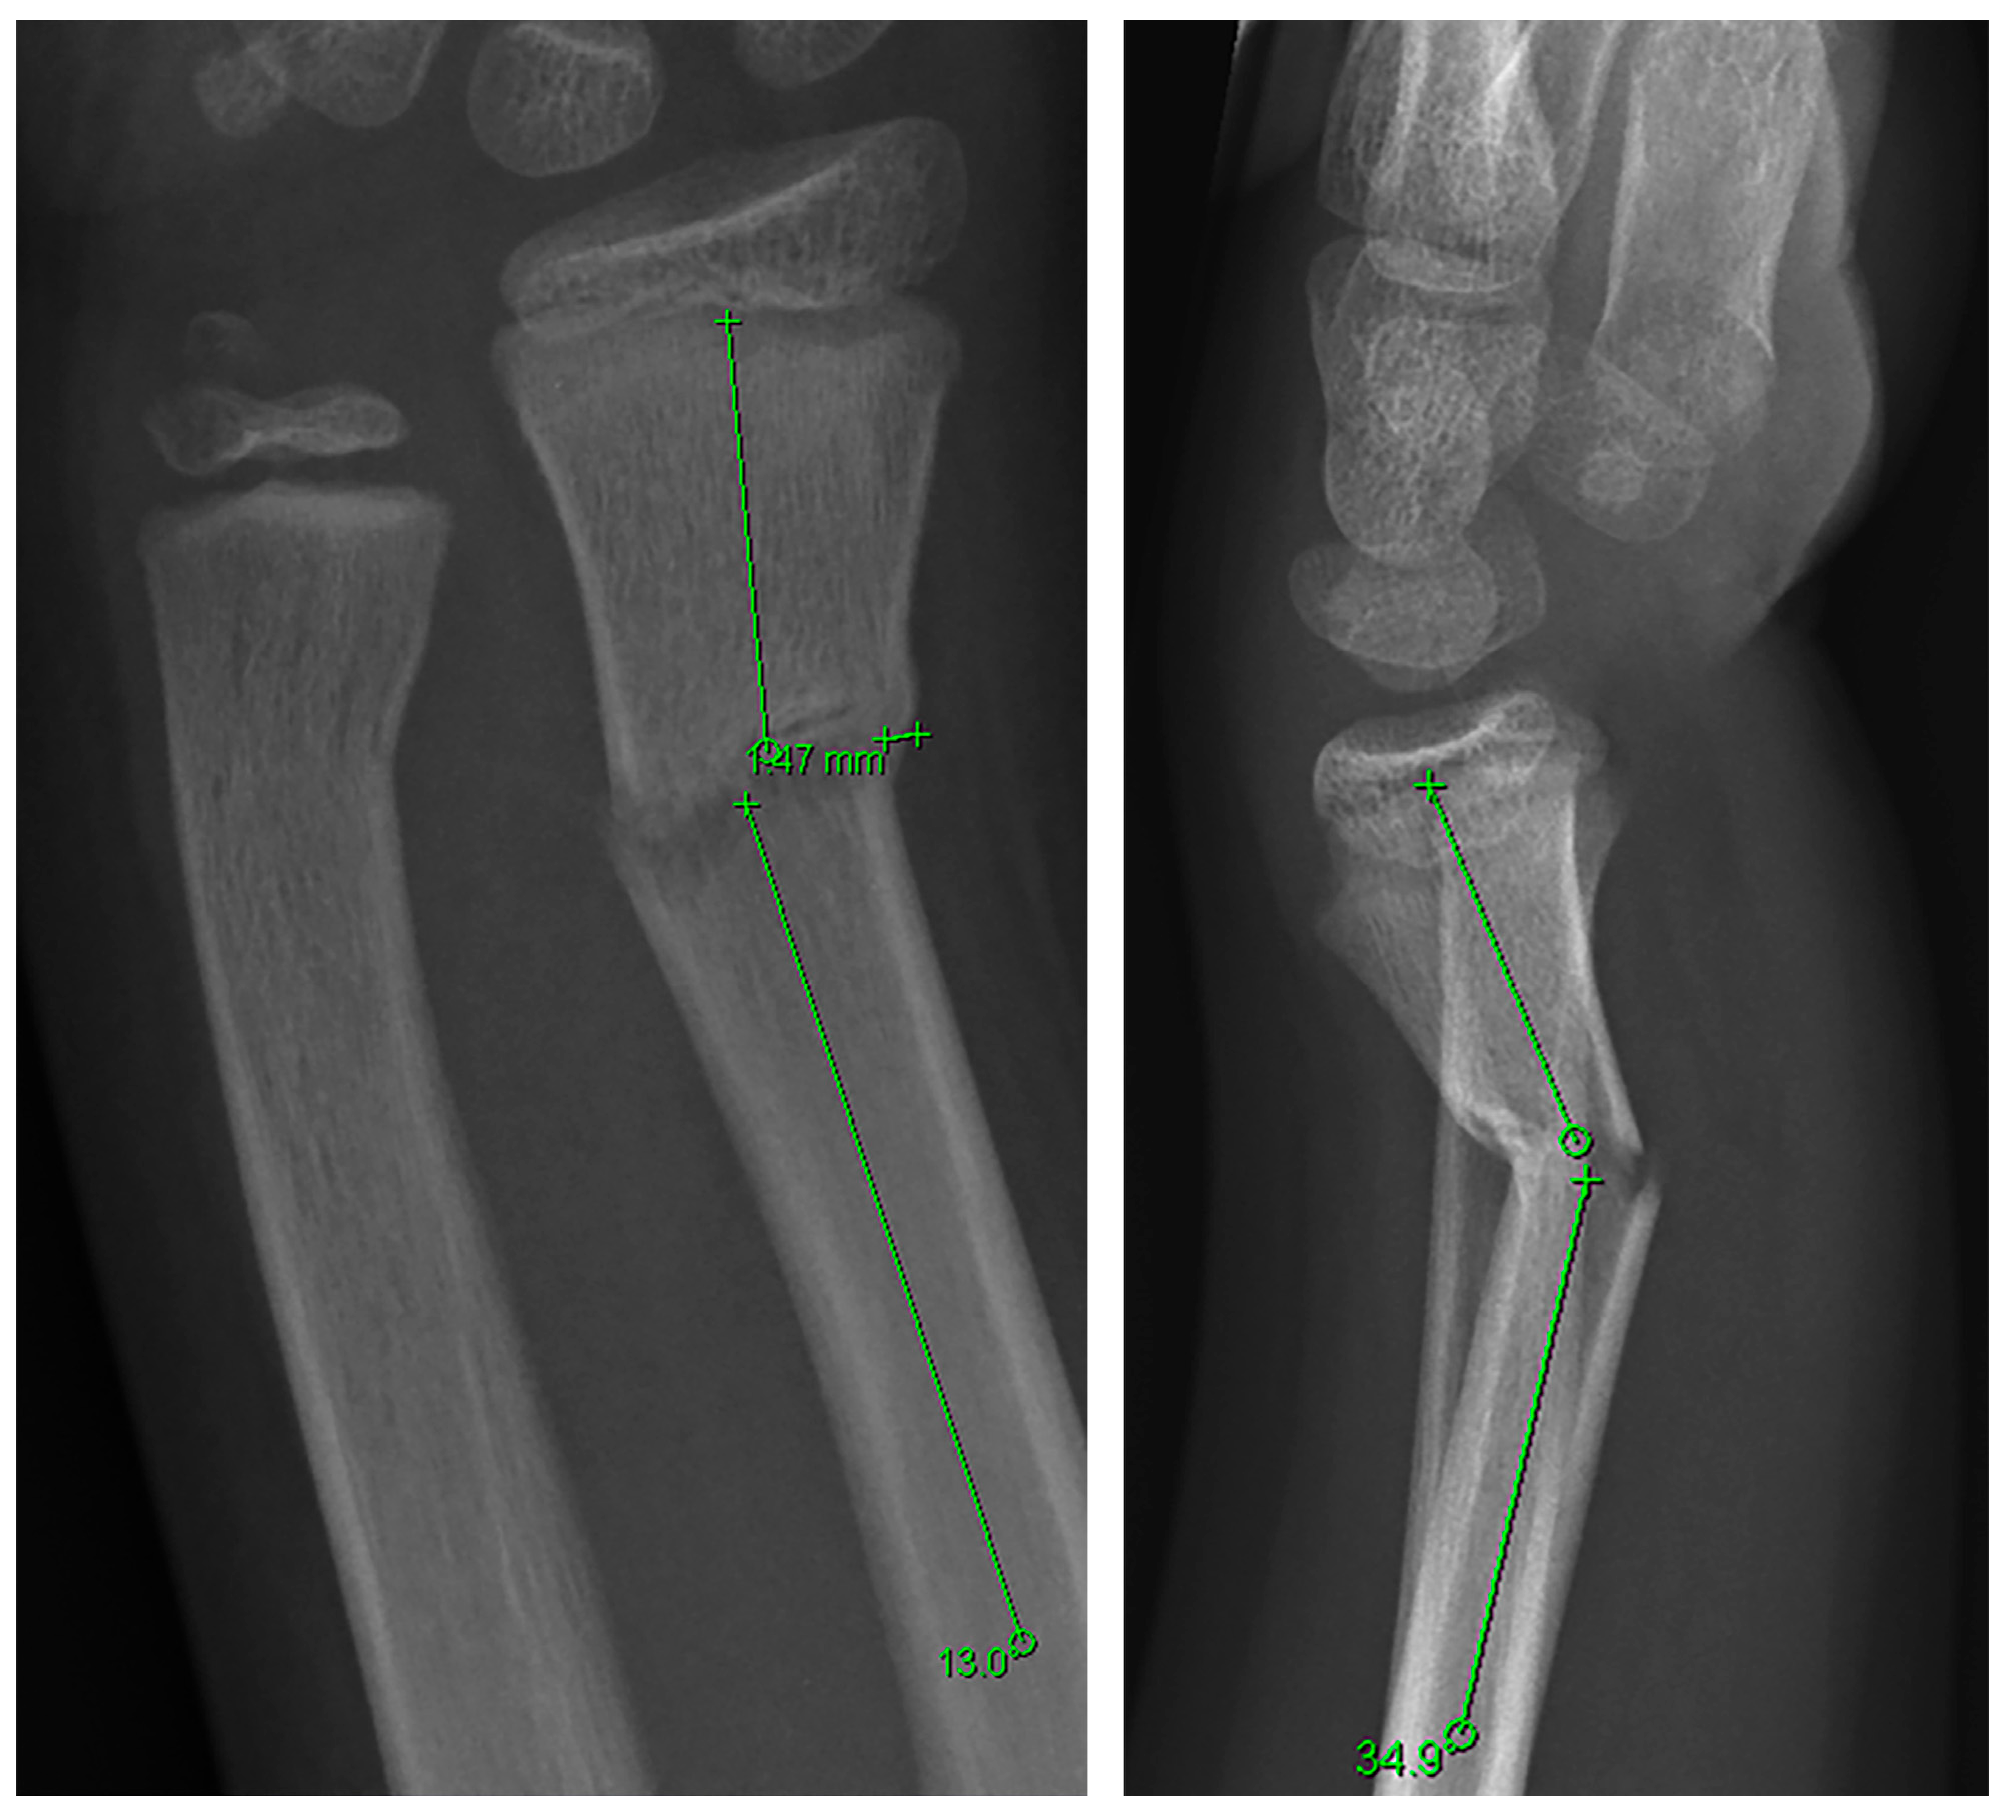

3.1.1. Distal Metaphyseal Fractures

3.1.2. Diaphyseal Fractures